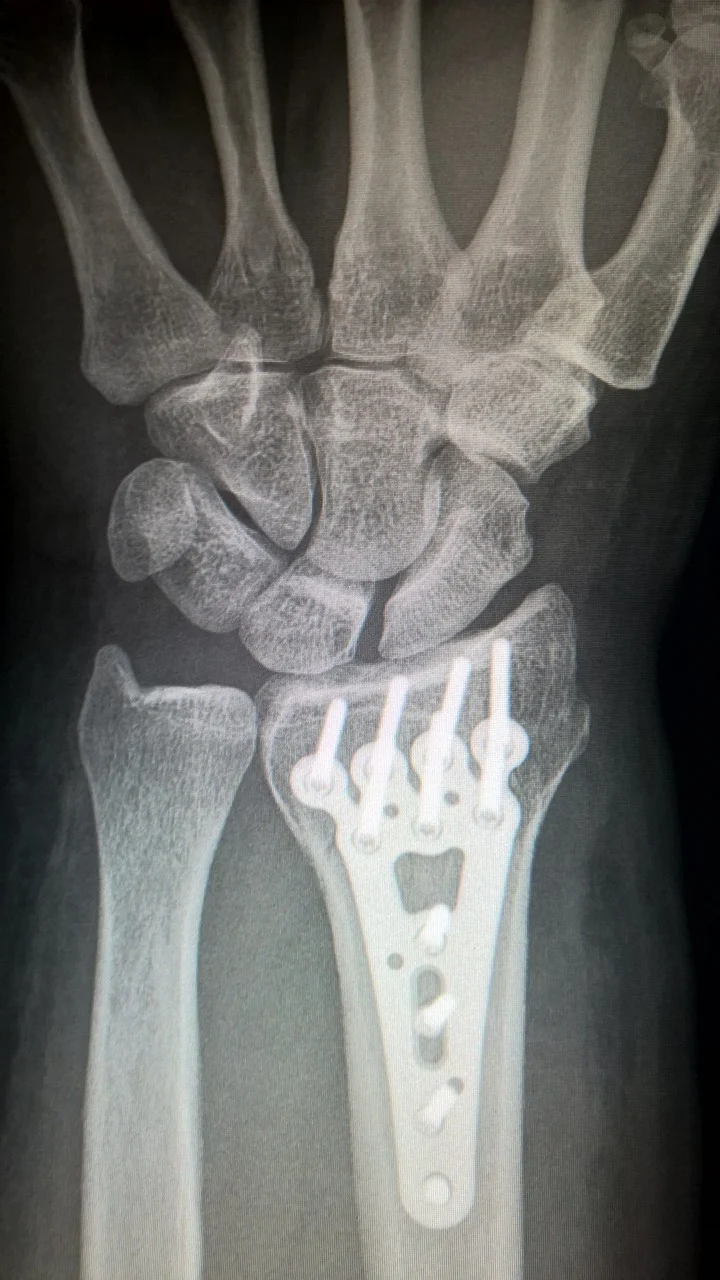

손목 골절이 발생하면 극심한 통증과 붓기가 수반되는데 방사선 촬영이나 CT촬영을 통해 골절 부위를 확인하게 됩니다. 손목 골절이 발생하면 대개 의사의 손이나 기구 등을 이용하여 골절 부위를 견인한 다음 이를 유지하기 위해 석고 고정(깁스)을 시행하게 됩니다. 그 후 정기적인 방사선 검사(X-ray)를 통해 고정 부위의 유지 여부를 확인하며 경과를 관찰하게 됩니다. 보통 깁스를 한 후 6주 정도가 지나면 골절 부위가 다시 고정이 되는데 깁스가 어렵거나 골절 부위에 깁스가 어렵거나 수술이 필요할 경우에는 골절 수술을 통해 치료를 하게 됩니다. 저도 유치원 다닐 때 미끄러져 정강이 부분이 부러진적이 있는데 그 때 2달 정도 깁스를 하고 있었던 기억이 있습니다. 그 당시 병원을 잘 선택했는지 뼈도 잘 맞춰지고 지금까지 성장하는데 문제가 없어서 다행입니다. 그 만큼 골절은 치료가 중요한 만큼 골절 시, 즉시 병원에 내원하셔서 치료를 받으시기 바랍니다.

최근에는 깁스보다는 수술적 치료를 권하는 경우가 많은데 예전에 깁스를 할 경우 손가락이 휘거나 뼈가 주저앉을 수도 있기 때문인데 최근 스포츠 활동의 중요성도 강조되고 있어 보다 적극적으로 수술적 치료를 고려하고 있다고 합니다. 특히 젊은 사람에게서 발생한 경우 정확하게 관절면을 맞추어 치료를 해야 하는 것이 중요하며, 오랜 기간 동안 깁스를 할 경우 손가락이 굳을 수 있기 때문에 지속적으로 손가락 운동을 권장하고 있습니다.